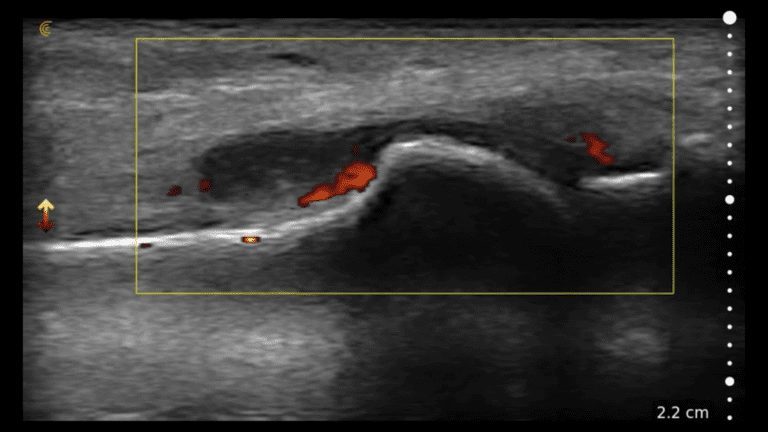

Dr. Alan Hirahara performs an intra-articular hyaluronic acid injection using ultrasound guidance to bring pain relief to a patient suffering from degenerative joint disease in her knees. Suprapatellar access to the knee joint space provides easy and painless entry even without a joint effusion present.

Suprapatellar Injection of the Knee

Dr. Alan M Hirahara, MD, FRCSC